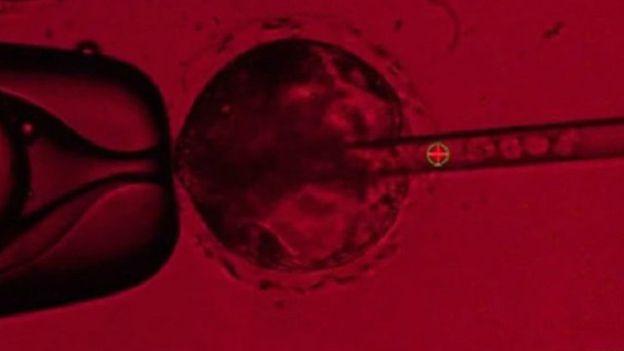

يمر إنتاج الأجنة عبر تعديل جين CRISPR لاستخدامه في إزالة “دي إن إيه” جنين الخنزير المخصب حديثًا بما يسمح للجنين الناتج بأن ينمو لديه بنكرياس.

وهذه الخطوة ستؤدي إلى تخليق جين “باطل”، وحينئذ يتم حقن الجنين بمحفز خلايا جذعية بشرية (iPS)، وهذه الخلايا مأخوذة من بالغين وتعالج لتصبح خلايا جذعية قادرة على التطور لخلية في الجسم.